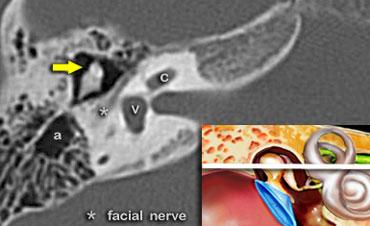

Đoạn nhĩ của dây thần kinh mặt

Trong hình ảnh này ở mức ống tai trong, đoạn nhĩ của dây thần kinh mặt được thấy nằm ngay phía trong và song song với thành của thượng nhĩ.

Đầu xương búa (mũi tên vàng) được thấy nằm phía trước đầu và mỏm ngắn của xương đe.

Hạch gối của dây thần kinh mặt

Ở mức này, ống thông hang (aditus ad antrum) được thấy rõ. Đây là đường thông nối giữa hòm nhĩ và hang chũm.

Đoạn mê đạo của dây thần kinh mặt xuất phát từ ống tai trong, chạy gần như vuông góc với trục dài của xương đá về phía trước để đến hạch gối (geniculate ganglion).

Tại hạch, dây thần kinh mặt tạo thành một vòng chữ U (gối thứ nhất của dây thần kinh mặt) để chạy ra phía sau như đoạn nhĩ dọc theo thành trong của thượng nhĩ.